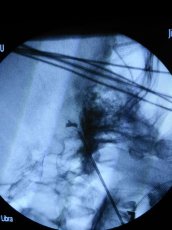

【顶尖技术看一院】市一院成功独立完成鲁西南首例 球囊压迫治疗三叉神经痛手术 让不愿开颅的患者多了一种治疗选择

一个球囊、一个针眼,不到一个小时,困扰患者半年三叉神经痛就被...